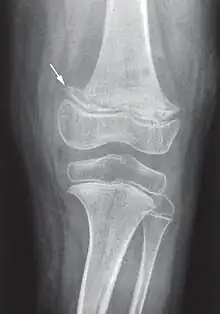

Les douleurs osseuses sont liées aux hémorragies sous-périostées. La radiographie peut montrer les troubles du périoste (hématomes sous-périostés) et de la structure osseuse (ostéoporose avec aspect en « verre pilé », la « ligne scorbutique » séparant la diaphyse des extrémités, élargissement de l'extrémité antérieure des côtes...)[21].